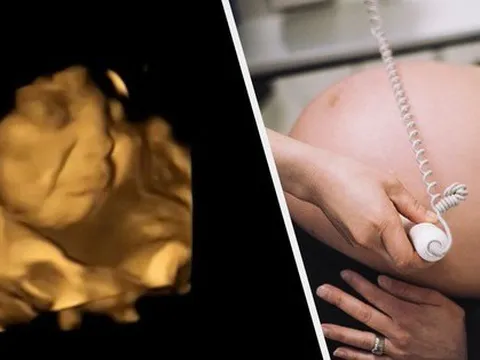

Thai nhi biết phản ứng khi ngửi thấy thức ăn trong bụng mẹ

Những đứa trẻ trong bụng mẹ thích cà rốt nhưng không thích nhiều rau xanh, và điều này thể hiện ngay trên khuôn mặt của chúng, theo nghiên cứu mới công bố ngày 22-9 trên tạp chí Psychological Science.